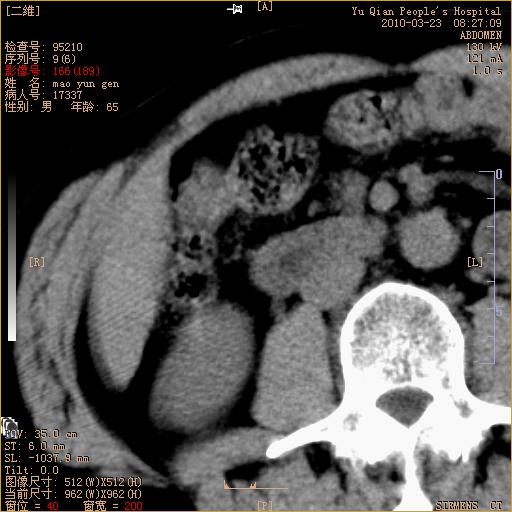

标题: CT25266:消瘦月余,前来肝部检查,请看看肠腔 [打印本页]

标题: CT25266:消瘦月余,前来肝部检查,请看看肠腔

肝区结肠占位,腺癌可考虑,建议肠镜活检。

升结肠肠壁增厚,不均强化,考虑升结肠腺癌可能性,建议肠镜检查。

1)考虑升结肠癌。2)右肾小囊肿。